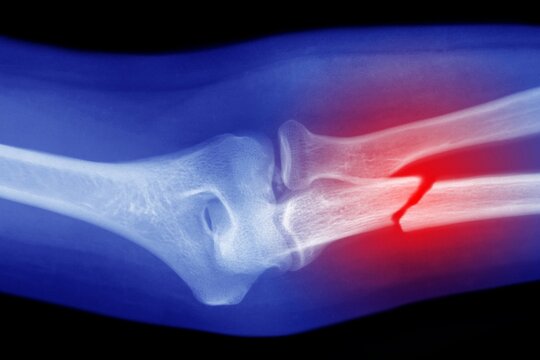

• Knochenbrüche